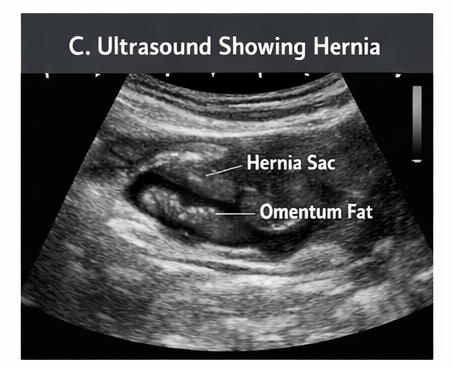

An abdominal ultrasound was performed to confirm the diagnosis and rule out complications:

These findings confirmed an uncomplicated umbilical hernia.

Ultrasound plays a supportive role in confirming the diagnosis and evaluating the contents of the hernia sac. It is particularly useful in differentiating umbilical hernia from other abdominal wall defects.